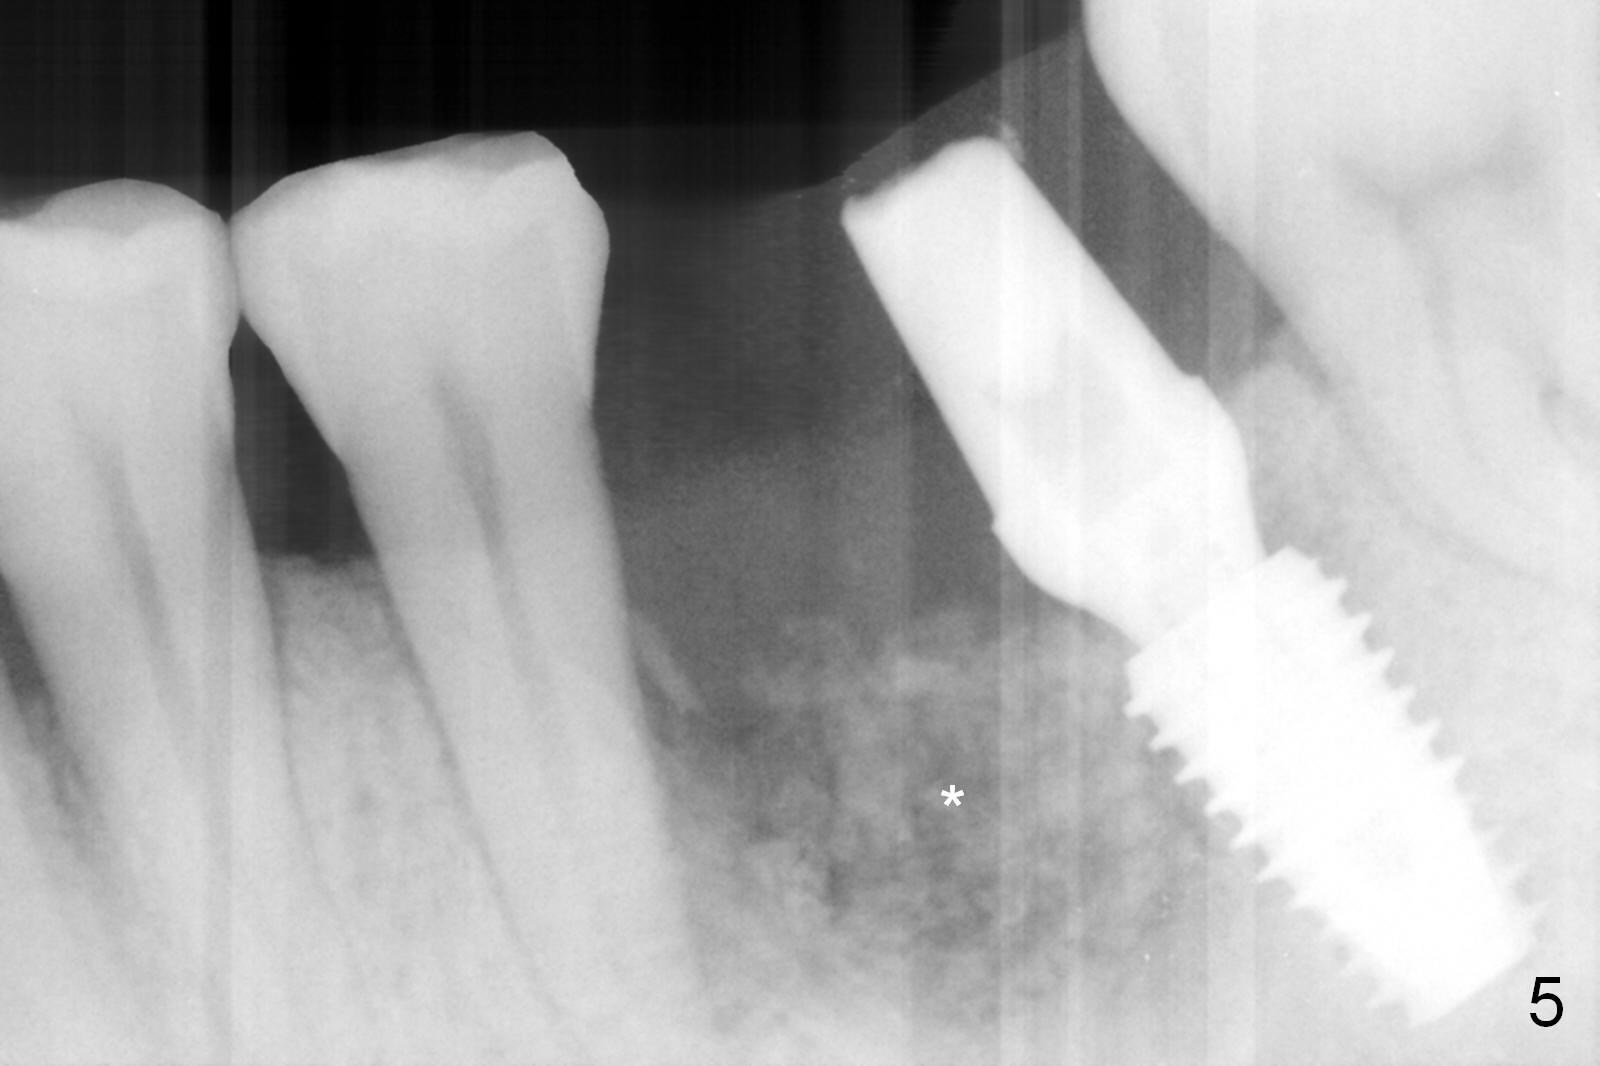

Considering the severe bone loss in the meisal socket, socket preservation is indicated if immediate implant is not feasible.  Preop exam shows that the mesiobuccal gingival recession (Fig.1 MB) is not as severe as the mesiolingual one (Fig.2 ML).  Because of oozing from the mesial socket, buccal envelop incision is made with flap raising to increase visibility.  Probably due to periodontal infection, pain control is difficult.  Osteotomy buccal to the Inferior Alveolar Canal proves to be risky.  In addition, osteotomy in the mesial socket is more difficult than the distal one (Fig.3).  Once the osteotomy depth is determined relative to the superior border of the Inferior Alveolar Canal (4 mm), the osteotomy depth increases by 2 mm.  A 5.5x10 mm implant is placed with insertion torque ~ 35 Ncm (Fig.4); a 15 ° angled abutment (5.5 mm in diameter, 4 mm in cuff) is placed mesially.  Then the abutment is turned lingually favorable for restoration (Fig.5), the remaining socket is filled with allograft/Osteogen (*) and Collagen Plug.